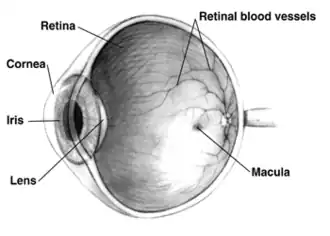

- 6 April – Japanese scientists announce that they have created working retinas from mouse stem cells.[114][115]

- Researchers in Oxford, England, begin human trials of a pioneering gene therapy technique, which is hoped to provide a cure for crippling ocular defects such as retinal choroideremia. (BBC)